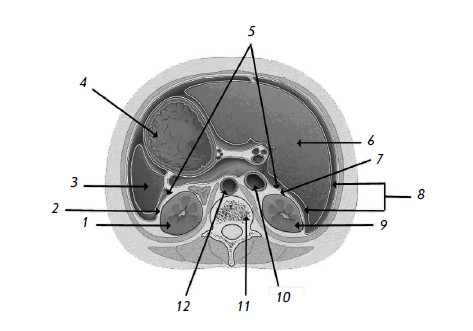

Рис. 2. Мочевая система (срез на уровне XII грудного позвонка, вид сверху)

1 – левая почка; 2 – околопочечная жировая клетчатка левой почки; 3 – селезенка; 4 – желудок; 5 – брюшина, покрывающая почки; 6 – печень; 7 – околопочечная жировая клетчатка правой почки; 8 – брюшная полость; 9 – правая почка; 10 – нижняя полая вена; 11 – XII грудной позвонок; 12 – брюшная часть аорты